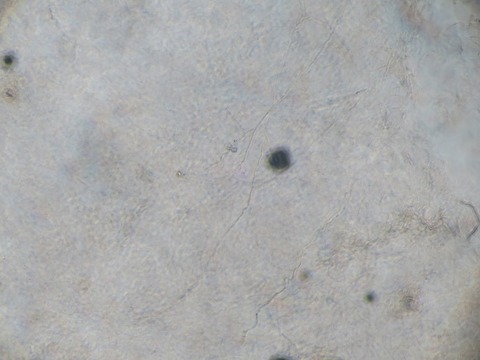

当院では、キャンデラ社のジェントル・マックス・プロによる医療レーザー脱毛を行っています。

アレキサンドライトレーザーとヤグレーザーを装備した最新型のレーザー機です。

肌色の濃い方、アレキサンドライトレーザーで残った体毛も照射可能です。